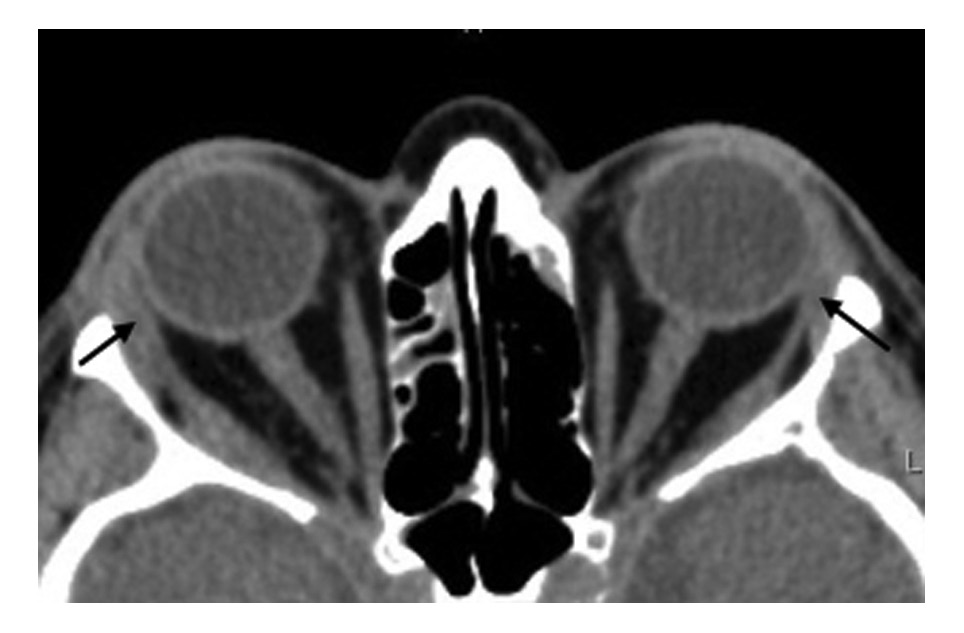

Через 6 мес после начала ухудшения отметила появление выраженного экзофтальма, болей в проекции правой орбиты, слезотечения, отеков век. Концентрация тиреоидных гормонов была в пределах нормы (ТТГ 1,22 мМЕ/л, свободного Т4 12,5 пмоль/л), содержание антител к рецептору ТТГ составляла 0,3 МЕ/л. Отмечались небольшое превышение содержания антител к ТПО до 22,7 МЕ/м (при норме до 5,6 МЕ/м), увеличение объема ЩЖ до 21 см3, умеренное снижение эхогенности с множественными мелкими гипоэхогенными зонами, неизмененная васкуляризация. При объективном исследовании обращали на себя внимание отек век, более выраженный справа, расширение эписклеральных сосудов, двусторонний экзофтальм, более выраженный справа (правый глаз (OD) 26 мм, левый глаз (OS) 22 мм), затруднение репозиции глазных яблок, вторичное косоглазие слева, нечеткость границ зрительного нерва при офтальмоскопии (рис. 1). Проведена МСКТ орбит: КТ-картина выраженного экзофтальма, утолщения глазодвигательных мышц (наружной и нижней прямых), значительное увеличение слезных желез (справа 30,0×15,8 мм, слева 25,0×11,5 мм, при норме: длина 5,4–12,9×2,7–6,5 мм), структура однородная, плотность снижена: справа 52 НU, слева 52 НU, признаки апикального сгущения справа (рис. 2).

Рис. 2. МСКТ орбит (аксиальная проекция) до лечения. Выраженное утолщение наружной прямой мышцы, увеличение слезных желез (стрелки).

Рис. 10. КТ орбит (аксиальная проекция) на сроке лечения 10 мес. Значительное уменьшение поперечника наружных прямых мышц и слезных желез (стрелки).

В результате иммуносупрессивного лечения отмечена выраженная положительная динамика: уменьшение экзофтальма, ретракции нижних век, регрессия косоглазия, бинокулярного двоения и периорбитальных отеков (рис. 9, 10). Лагофтальм на правом глазу не регистрируется. На сроке наблюдения 10 мес ремиссия воспалительного процесса в орбите сохранялась на поддерживающей дозе глюкокортикоидов.